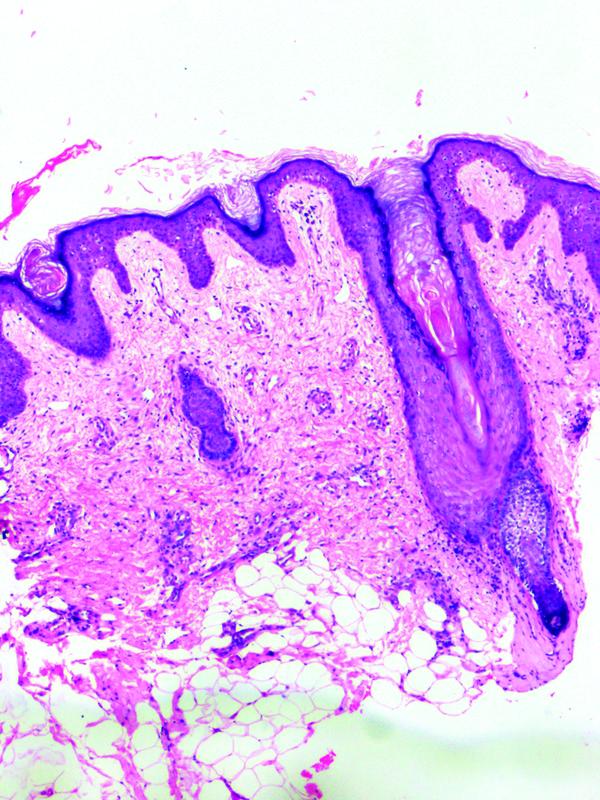

Histopathological examination of the papules revealed orthokeratotic follicular plug, mild superficial dermal edema, perivascular, and focal perifollicular lymphohistiocytic infiltrate. The rest of the epidermis, deep dermis, and subcutis were unremarkable ([Fig. 2]). The clinicopathological correlation and literature search rendered the diagnosis of sorafenib-induced SFH and grade 1 hand-foot skin reaction (HFSR).

| Figure 2: (A) Orthokeratotic follicular plug, mild superficial dermal edema, perivascular and focal perifollicular lymphohistiocytic infiltrate (hematoxylin and eosin x 100).

SFH is one such rare and peculiar dermatological disorder, first identified by Joncas et al and Lopez et al, and later reported by Franck et al, in 21%-of patients receiving sorafenib.[3] [4] [5] It is characterized by flesh-colored or white, follicular hyperkeratotic spicules, preferentially involving the face, scalp, upper trunk, and upper arms.[5] [6] [12] It is asymptomatic, devoid of erythema, and appeared 9 to 164 days after treatment initiation in the patient cohort described by Franck et al.[5] Though our patient had a morphologically identical presentation, she exhibited a shorter time-to-onset of SFH, that is, 7 days, and sparing of upper trunk and arms. Follicular dilatation with hyperkeratotic follicular plug and perifollicular lymphocytic infiltrate are the histopathological attributes shared by all SFH cases, including ours.[3] [4] [5] [12] [13] [14] [15] [16] The orthokeratotic digitate spike protruding above the epidermis, a distinct feature demonstrated in one out of the four cases evaluated by Franck et al, was probably lost in the tissue processing of our case.[5]